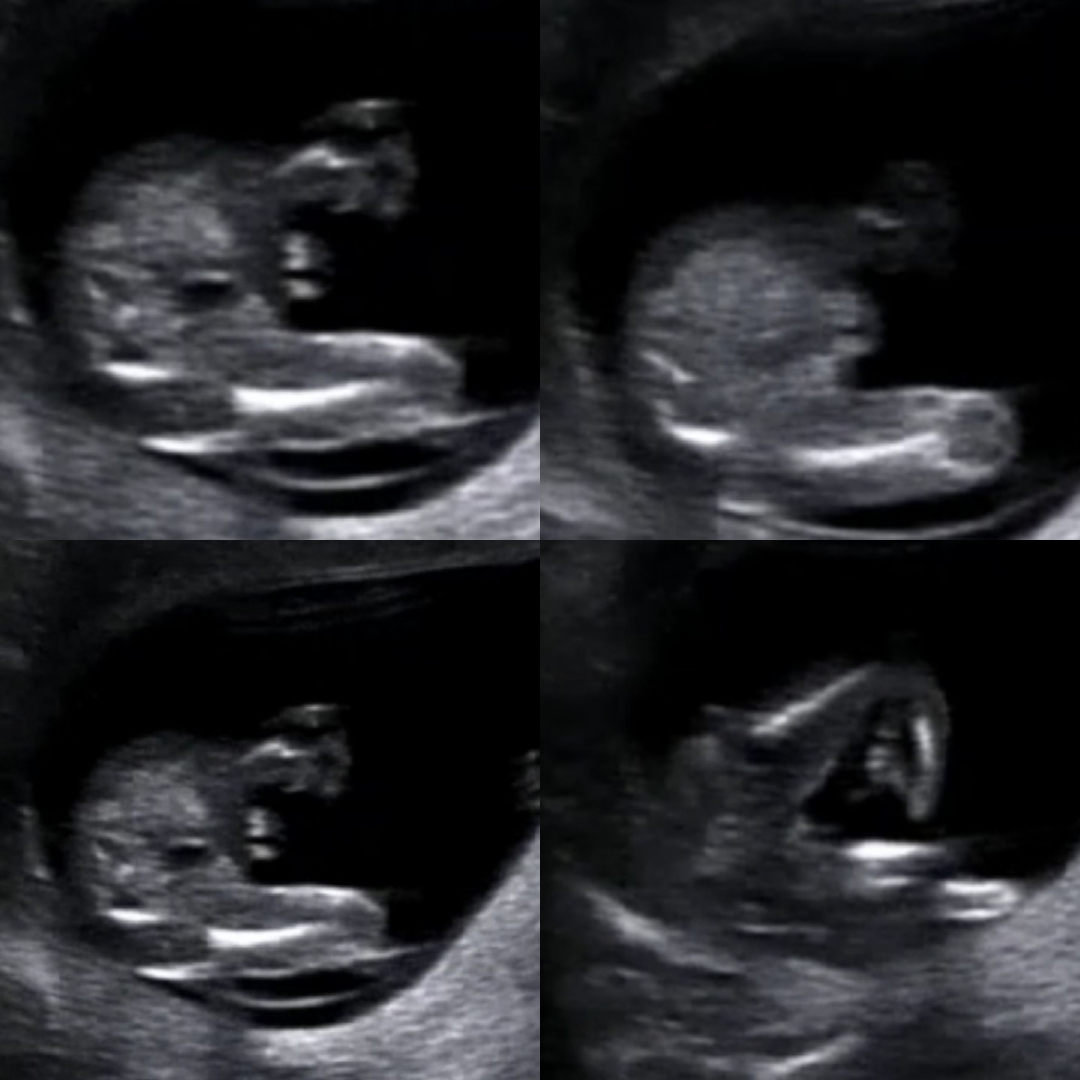

아들인듯? 딸인듯? 🤣 한번씩만 봐주세요 🙇♂️ (14주)

12주 각도법으로는 다들 딸이라고 하셨는데 뭐가 있는듯 없는거 같으면서 탯줄 같기도 하고ㅎ 어떻게들 보시나요? 편하게 부탁드려요 !

저이번에 저렇게 동그랗게 보였는데 이건 탯줄이에요~ 하셨어요

저렇게 동그랗게 보이는건 탯줄같아요 마지막은 딸인것같구요!!